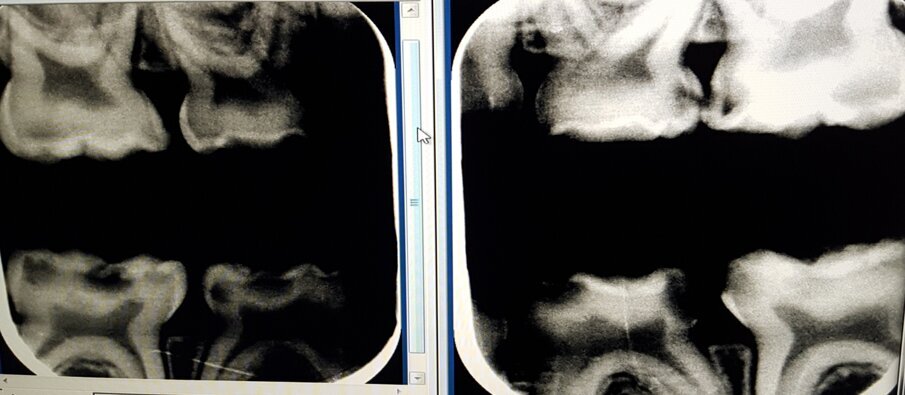

Een jong kind werd in 2016 verwezen voor behandeling met een kroon onder narcose van de 55. Ik zag daar geen reden toe en behandelde de molaar volgens de ART-methode. Bij een ander kind met dezelfde indicatie paste ik SMART toe: SDF in combinatie met ART. Bij evaluatie na 3 jaar was het resultaat bij beiden bevredigend (afb. 4a-b).

De SMART-methode heb ik ook bij een meisje van tweeënhalf jaar uit de VS toegepast. Diagnose: amelogenesis imperfecta. De klacht: hypersensitiviteit en cariës. In de VS luidde de indicatie: 20 kronen plaatsen onder narcose. In plaats van de behandeling met kronen werden zonder narcose bij het kind in twee zittingen behandelingen uitgevoerd met de SMART-methode. Dat was afdoende om de klachten te bestrijden. Een paar maanden later stuurden de ouders uit de VS het bericht dat het goed ging met hun kind. De laag glasionomeercement was ook nog aanwezig. Na 27 maanden zag ik het kind weer. Zij was klachtenvrij. De coating met glasionomeercement was geheel of gedeeltelijk verloren gegaan, maar de laesies zijn stabiel en restauratieve herbehandeling is vooralsnog overbodig (afb. 5a-b).

Afbeelding 5a. Diverse SMART-restauraties na 27 maanden verloren gegaan, maar de laesies zijn geïnactiveerd; reparatie daarom niet nodig.

Afbeelding 5b. Diverse SMART-restauraties na 27 maanden verloren gegaan, maar de laesies zijn geïnactiveerd; reparatie daarom niet nodig.